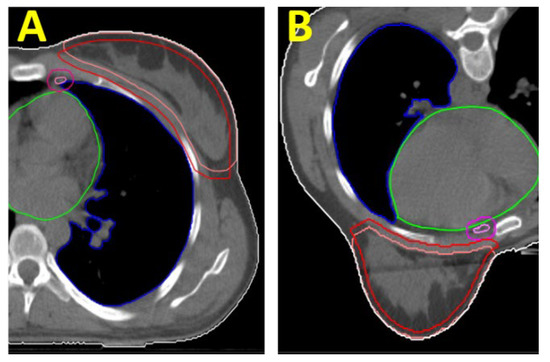

For 3D planning, we used a tangential technique in the prone and the supine positions, deploying 6 MV photon main beams and extra 15 MV photon beams for homogeneity. In IMRT planning of PTV “B”, we only used 6 MV: in the prone position, a multibeam IMRT approach with about 30 segments, and in the supine position, a tangential IMRT with about 30 segments (Figure 1). For covering PTV “B + PSR”, IMRT consisted of up to 45 segments.

Figure 1. (A): Illustration of the main EBRT directions for the IMRT technique for treating the breast (PTV “B”) in the supine position (“tangential IMRT”). Also shown is the contour of the CTV “Breast” (light red) and PTV “B” (red), as well as the OARs “heart” (green) and ipsilateral lung (blue). (B): Main EBRT directions for the IMRT technique for treating the breast in a laterally tilted prone position (“multibeam IMRT”).